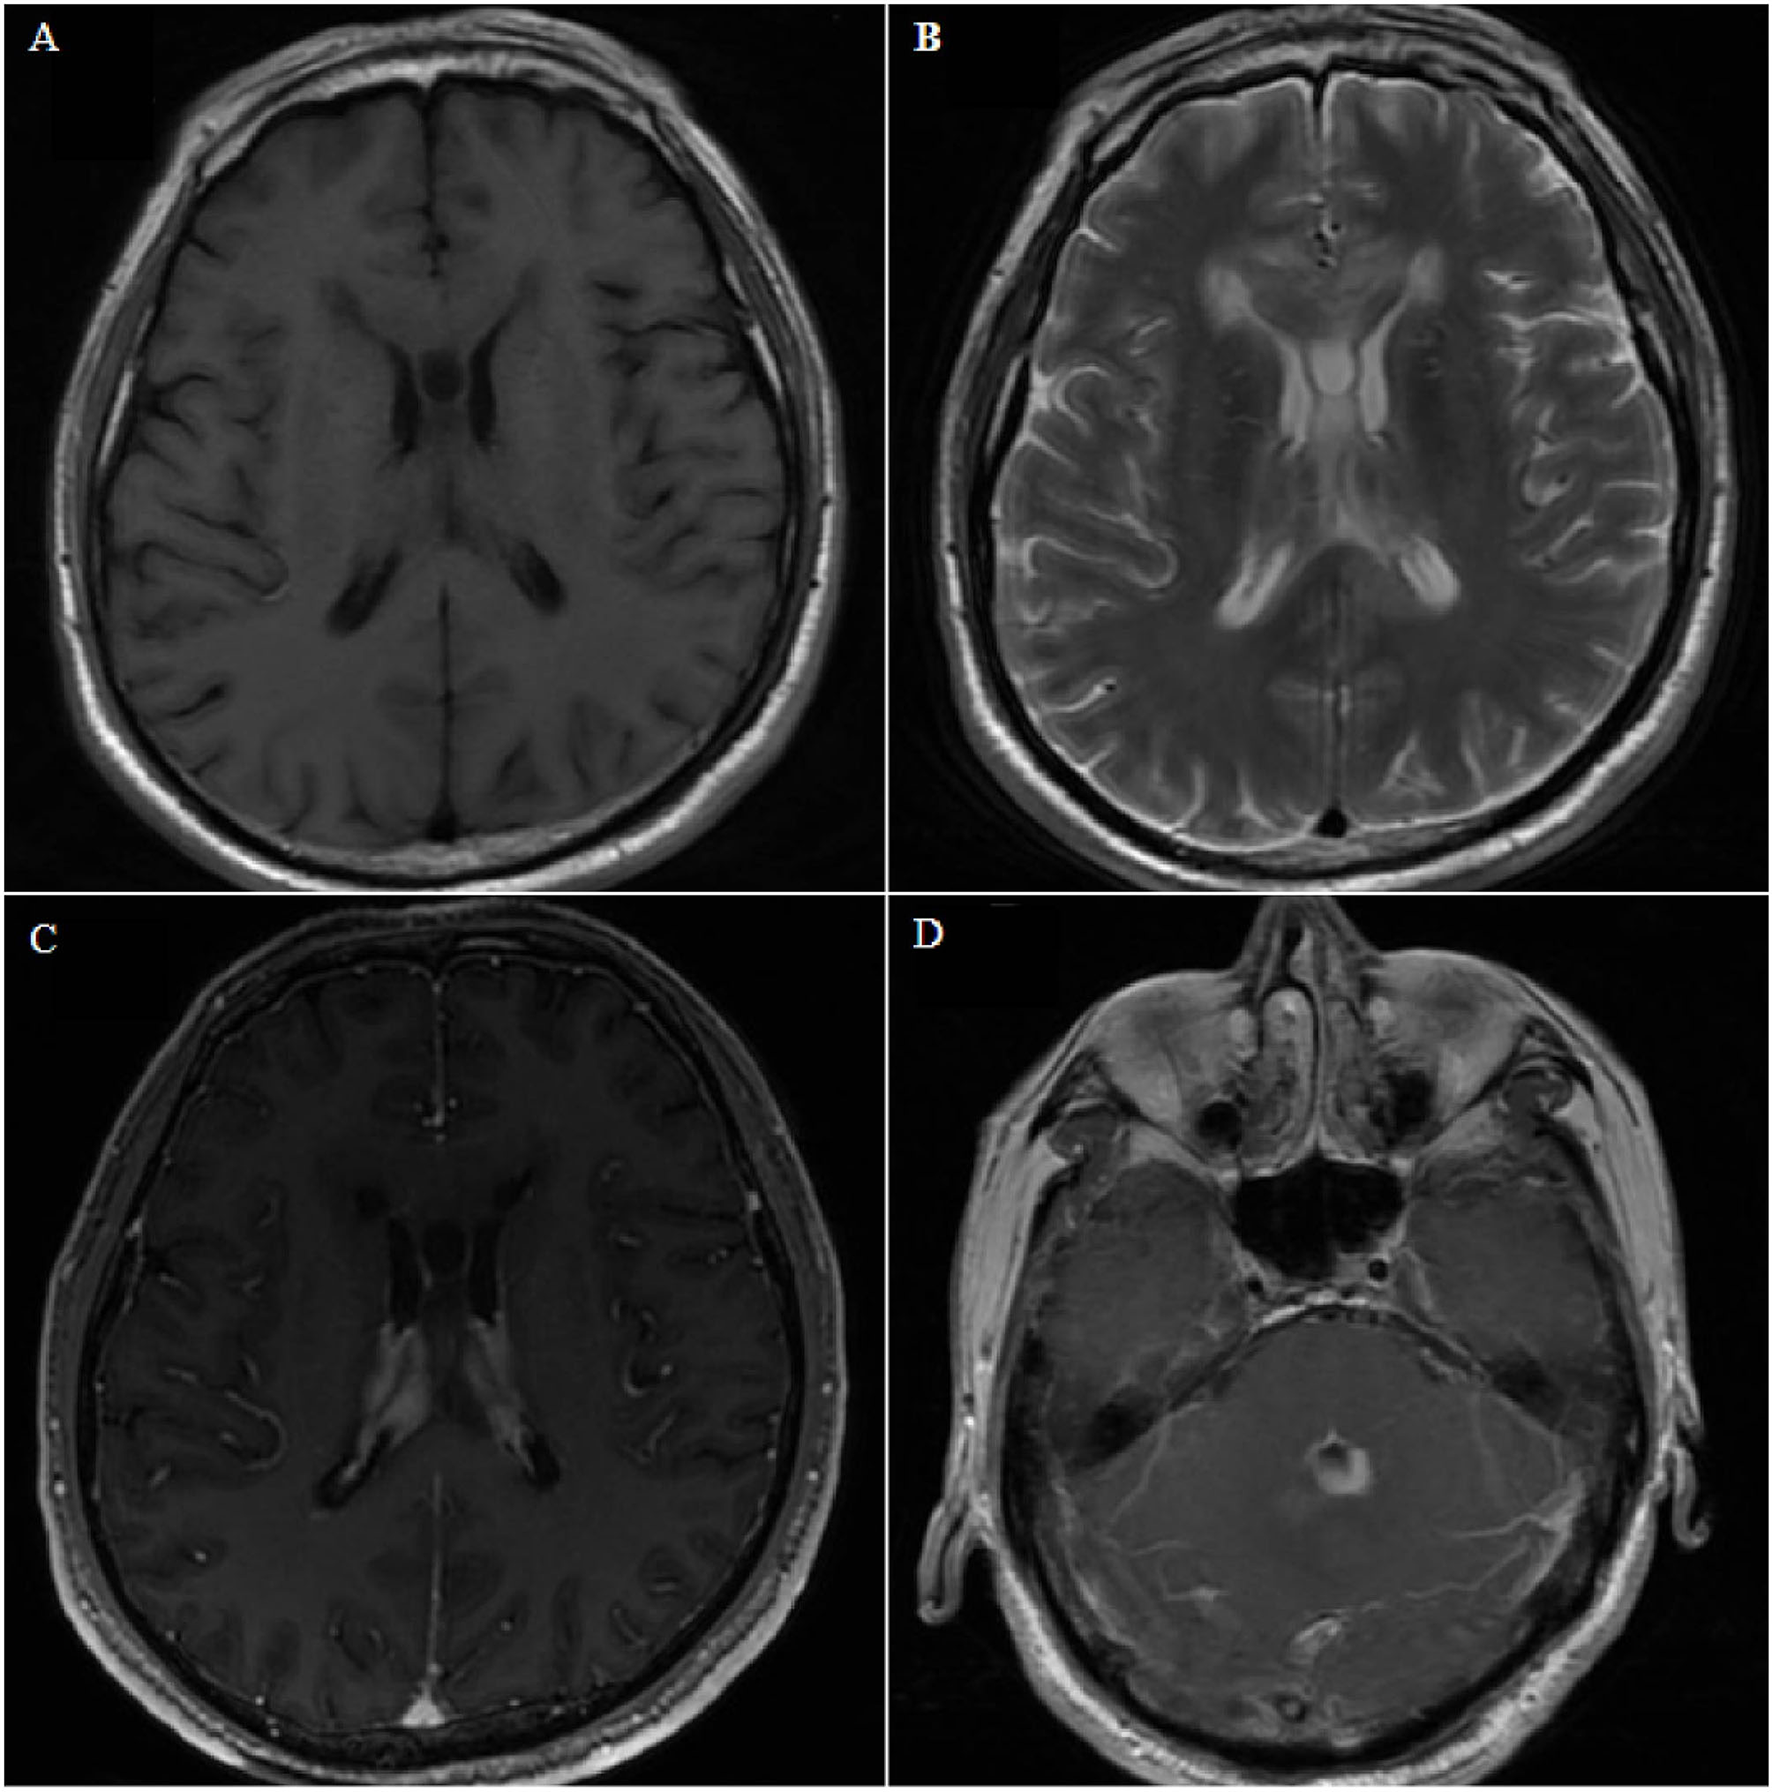

Case 8. Axial magnetic resonance image showing bilateral and fourth ventricle lesions, diffuse growth along the choroid plexus and ventricle wall, low signal on T1- and T2-weighted images (A,B), and homogeneous enhancement on contrast-enhanced T1-weighted images (C,D).

A 67-year-old man presented with gait instability for 20 days, and he had no history of underlying diseases. MRI examination revealed lesions in bilateral ventricles and the fourth ventricle (Figure 4), which could not be diagnosed clearly before surgery. After microsurgical resection, the lateral ventricular lesion was partially resected. Postoperative pathology revealed diffuse large BCL. Postoperative systemic examination revealed no other systemic lymphoma. The family refused further chemotherapy, and the patient died 1 month later.